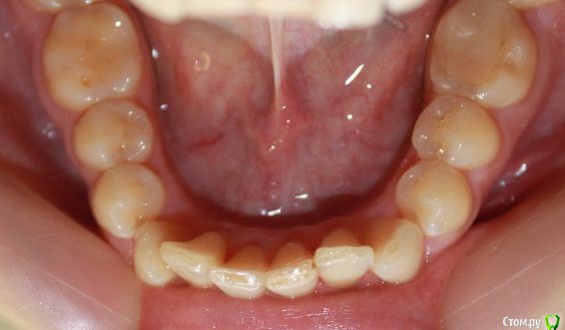

kapyulia Опубликовано 22 декабря, 2017 Поделиться Опубликовано 22 декабря, 2017 Добрый день! Могли бы Вы подсказать есть ли необходимость в удалении зубов (пятерки) с верхней челюсти? Спасибо за помощь. Ссылка на комментарий

Brigita Опубликовано 24 декабря, 2017 Поделиться Опубликовано 24 декабря, 2017 Сложно сказать без очного осмотра, по фото показаний нет. Ссылка на комментарий